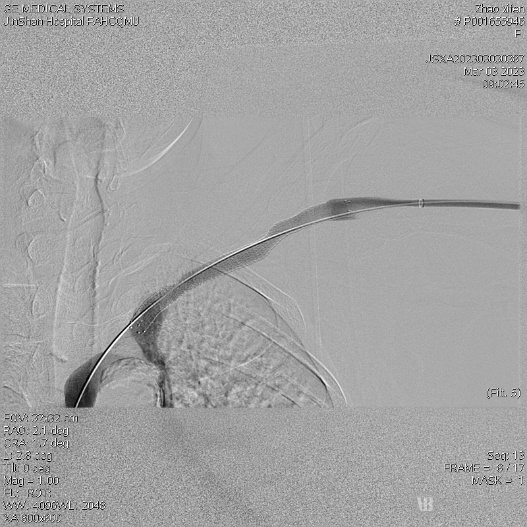

术后造影